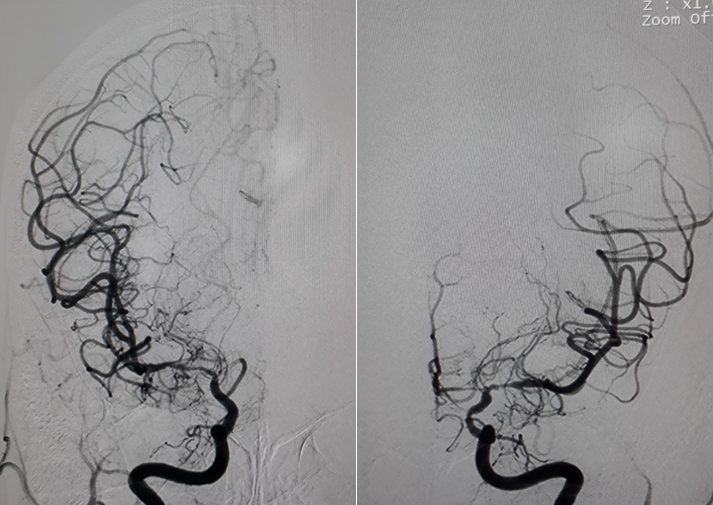

Hình chụp DSA động mạch cảnh trong phải và trái: hẹp khít động mạch não giữa hai bên đoạn M1.

Hình chụp DSA động mạch cảnh trong trái: hẹp khít động mạch cảnh trong trái đoạn mấu giường.

Hình chụp DSA động mạch đốt sống: bàng hệ cho hệ tuần hoàn trước từ hệ thống tuần hoàn sau